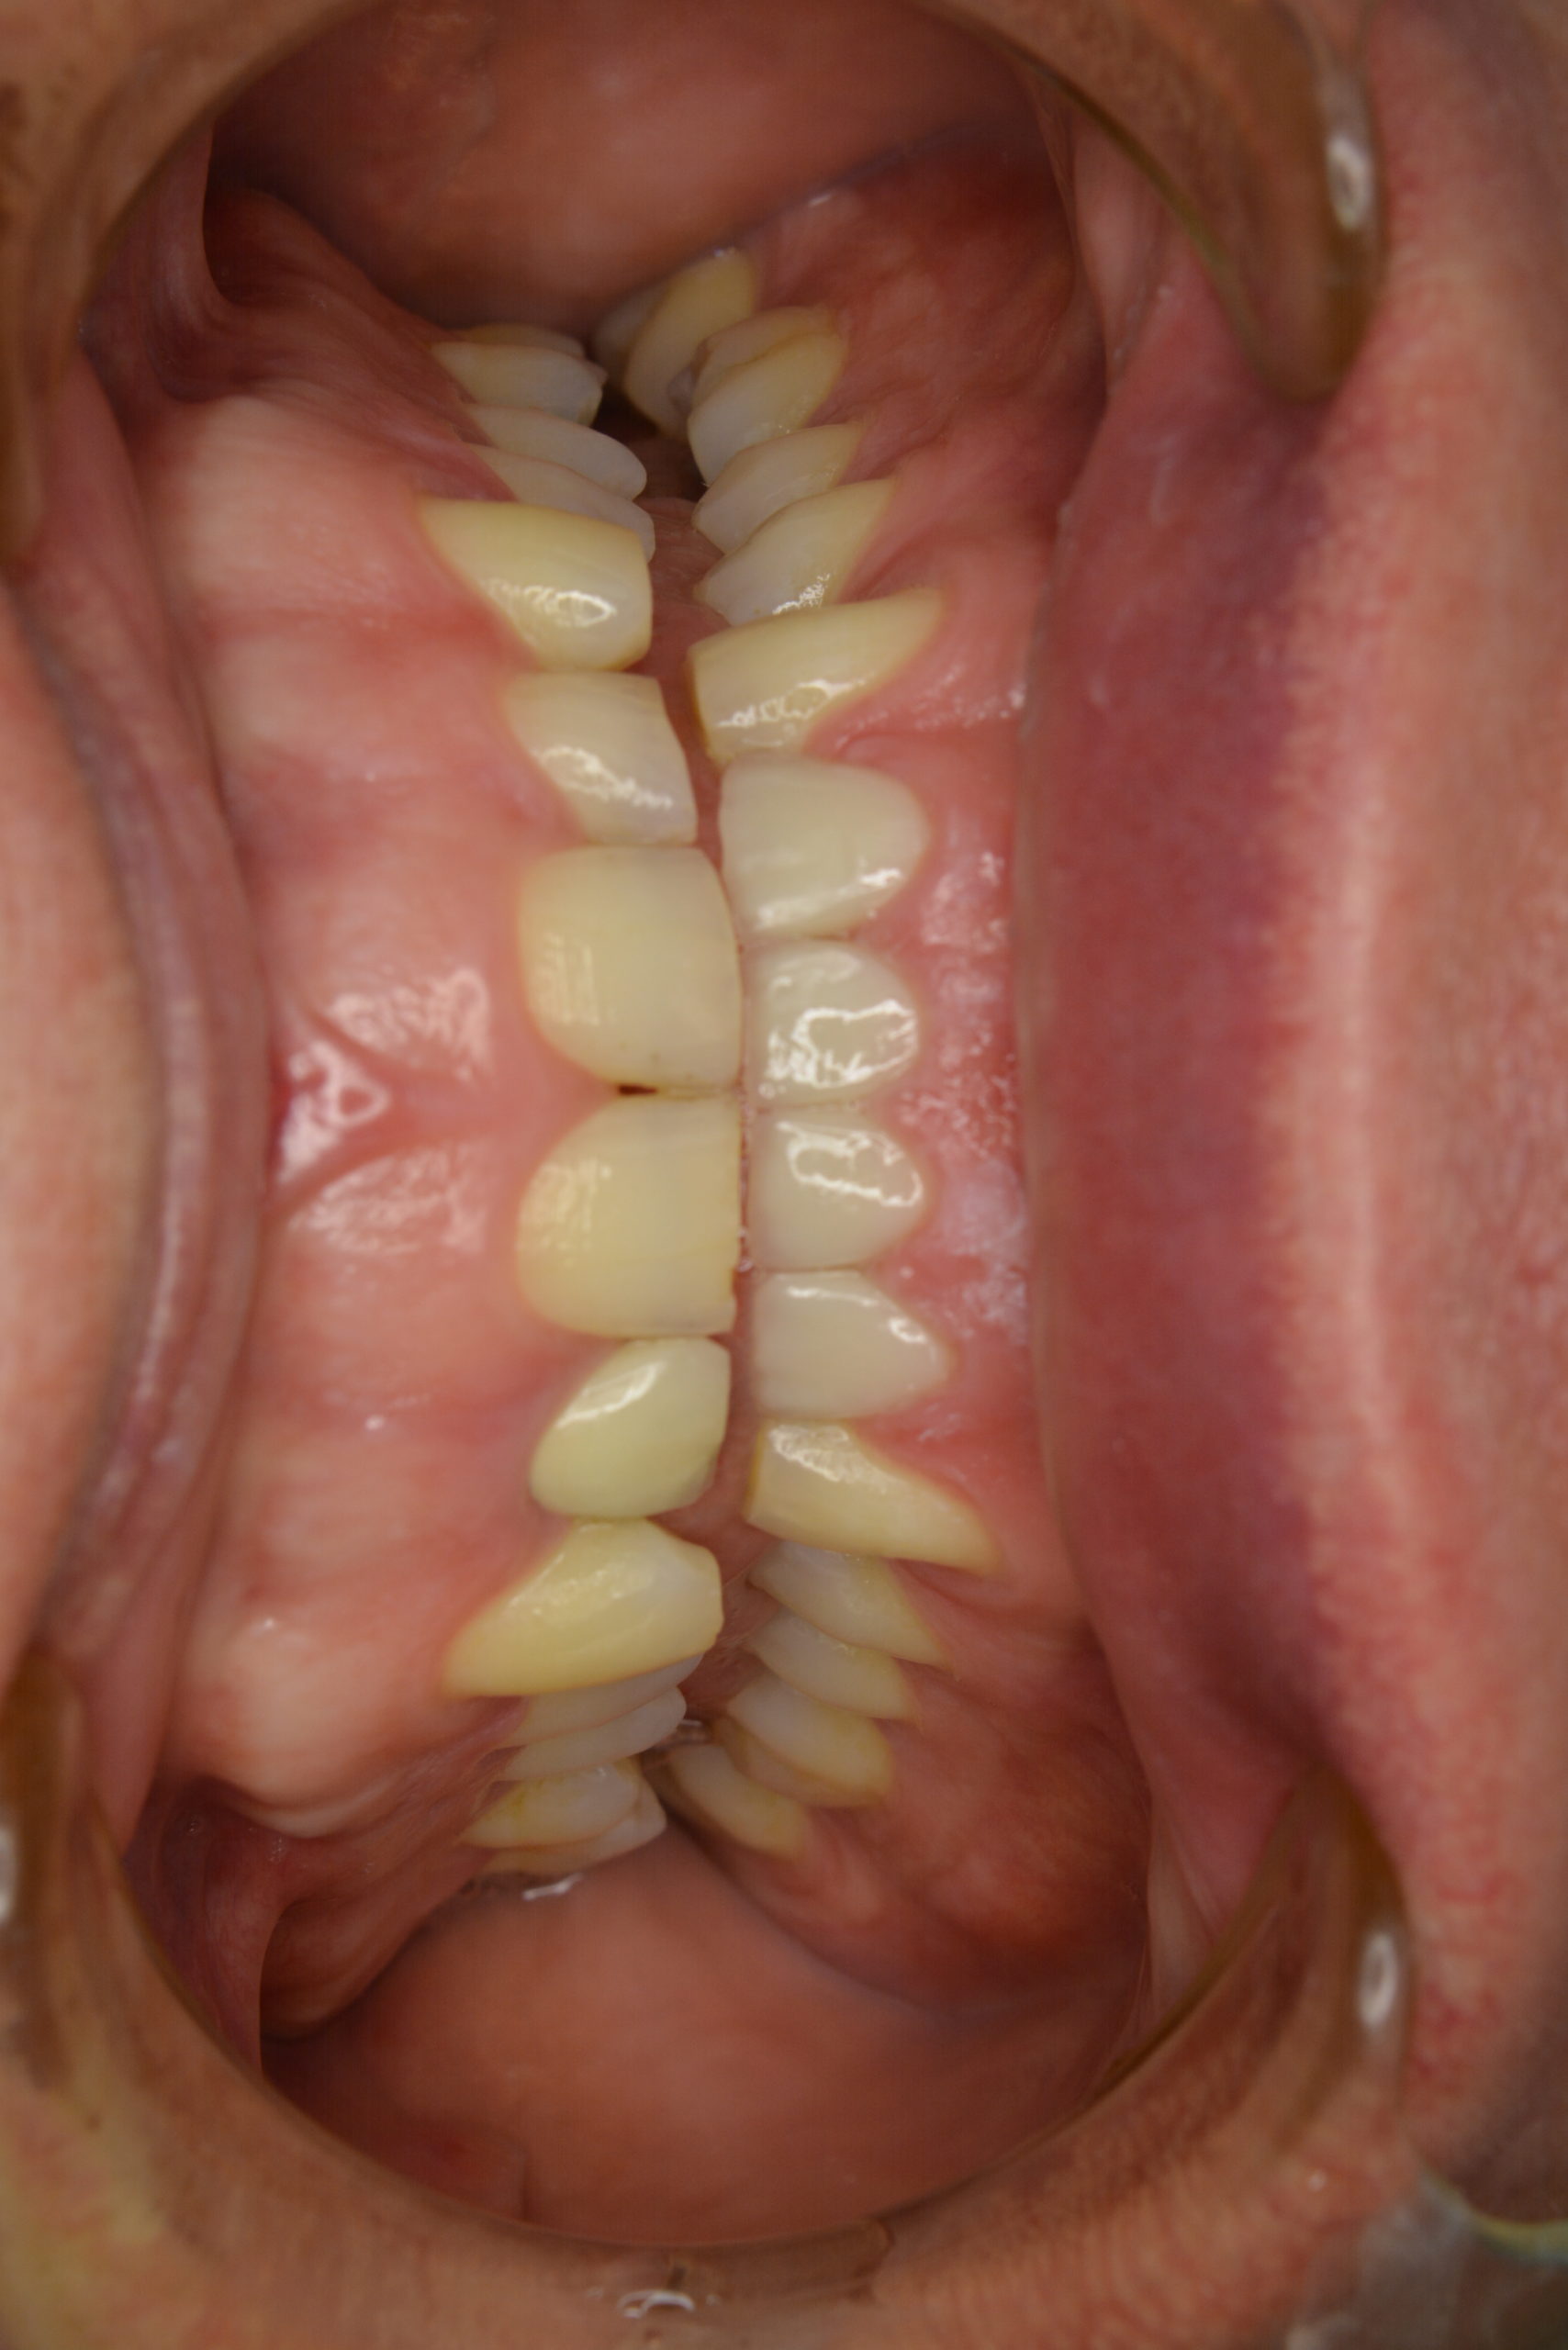

I’ve always had small teeth. But in the 40-odd years that I’ve had my adult teeth, I’ve managed to wear them out a bit. Well, quite a bit. And my dentist referred me to a restorative dentist in 2011. After much examination and photography, I was presented with a report which told me that I needed to have four crowns on my lower incisors fairly urgently and six further crowns on my top incisors at some point after that.”

Minor tooth grinding during sleep often results in this problem later on in life. For those early on in life a night guard is recommended, and for those already suffering from short and worn lower teeth, the teeth should be built up with crowns and a night guard should be worn from then on to keep them in shape.